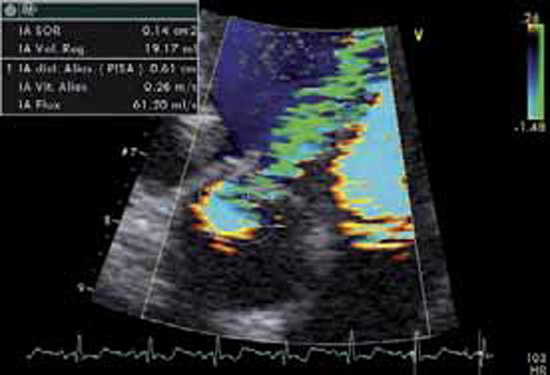

Figure 2 : Zone de convergence du flux régurgitant

En amont de l’orifice aortique, le flux décrit un hémisphère au doppler couleur, c’est la « zone de convergence » ou PISA, dont l’importance permet de quantifier l’IA.